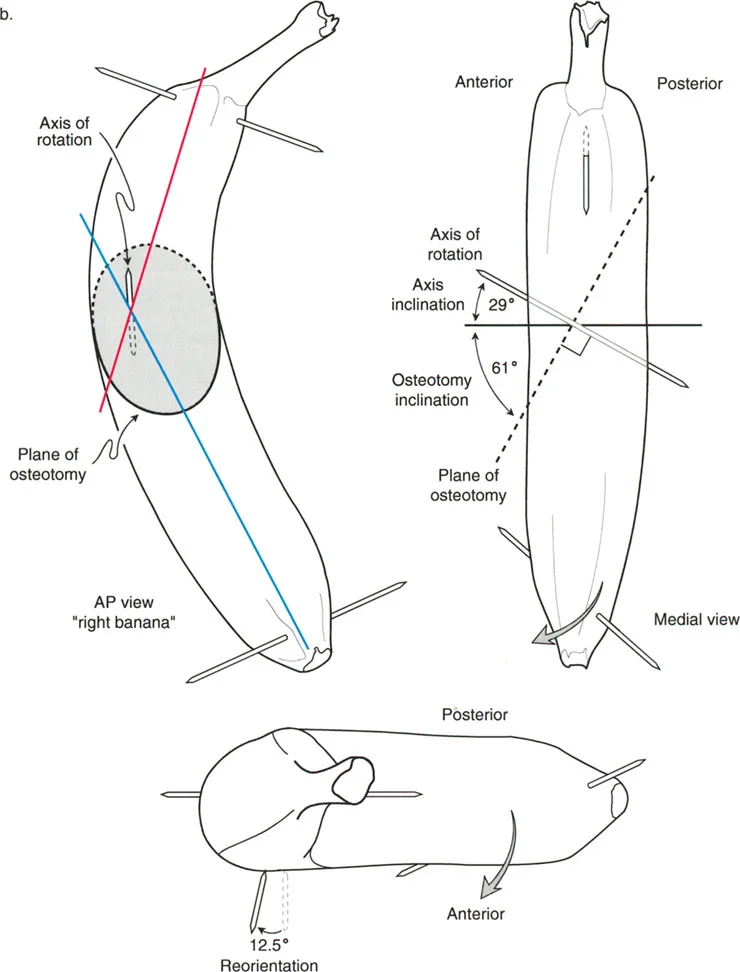

التصوير المقطعي المحوسب (CT Scan)

في بعض الحالات، خاصةً عند وجود تشوهات دورانية أو لتحديد شكل العظم ثلاثي الأبعاد بشكل أكثر دقة، قد يطلب الدكتور هطيف إجراء فحص CT.

التخطيط الجراحي الحاسوبي المتقدم

بعد جمع كل هذه البيانات، يستخدم الدكتور هطيف برامج حاسوبية متخصصة لإجراء تخطيط جراحي دقيق للغاية. هذا التخطيط يسمح له بـ:

* محاكاة الجراحة: رؤية كيف سيبدو الطرف بعد التصحيح قبل إجراء أي قطع.

* تحديد مستوى قطع العظم (Osteotomy Level): اختيار أفضل مكان لقطع العظم.

* تحديد محور تصحيح الزاوية (ACA): تحديد النقطة المحورية التي سيتم حولها تدوير العظم.

* حساب مقادير التصحيح: تحديد مقدار الزاوية التي يجب تصحيحها بدقة متناهية.

مستوى قطع العظم (Osteotomy Level)

مستوى قطع العظم (الشق الجراحي) يقع بالكامل تحت سيطرة الجراح. تحدد العلاقة الهندسية بين مستوى قطع العظم، وACA، وCORA النوع الدقيق للتصحيح الناتج، وتحدد ما إذا كان سيحدث تشوه ثانوي غير مقصود (مثل الانزياح غير المرغوب فيه).